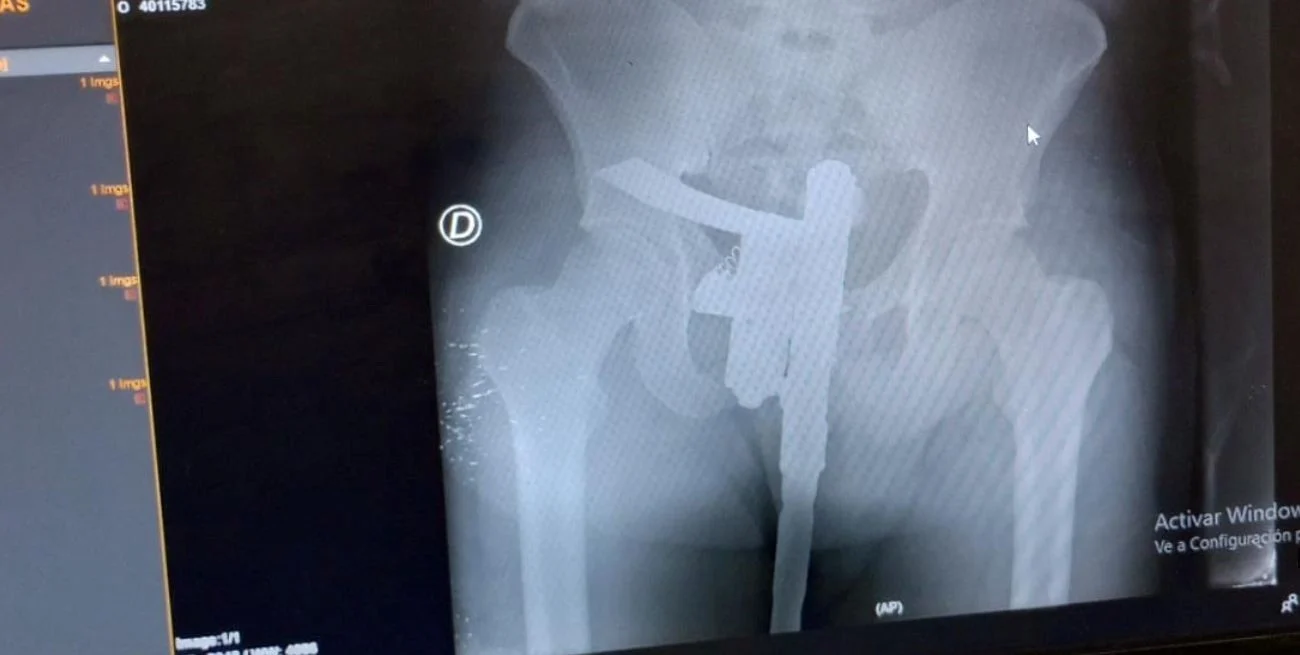

Un joven de 25 años fue al hospital Cullen de la capital provincial luego de haber sufrido un accidente vial, manifestó que le dolía la cadera, cuando le realizaron una radiografía descubrieron que ocultaba un arma de fuego en sus genitales.

Un joven de 25 años de la ciudad de Santa Fe que estaba internado en el Hospital Cullen tras sufrir un accidente vial el pasado domingo, fue detenido tras hacerle una radiografía y descubrir que portaba un arma de fuego entre sus genitales.

El desconcierto comenzó cuando los médicos del hospital le realizaron una radiografía diagnóstica, pues el hombre manifestaba tener dolor en la zona de la cadera producto de los golpes.

Tras obtener la imagen, los galenos descubrieron que portaba un arma de fuego de fabricación casera en la zona de los genitales.

Inmediatamente dieron aviso a agentes del Destacamento número 11 que funciona dentro del mismo lugar, quienes procedieron a secuestrar la pistola y detener preventivamente al portador.

Posteriormente, fueron notificadas las autoridades policiales de la Comisaría cuarta de Santa Fe, que aguardaron a que el joven recibiera las curaciones pertinentes y lo trasladaron al edificio policial.

La fiscal en turno del Ministerio Público de la Acusación, Gabriela Arri, ordenó que el muchacho siga privado de su libertad, y solicitó que sea identificado a la brevedad, para que le sea formada una causa por el delito de tenencia indebida de arma de fuego de uso civil.